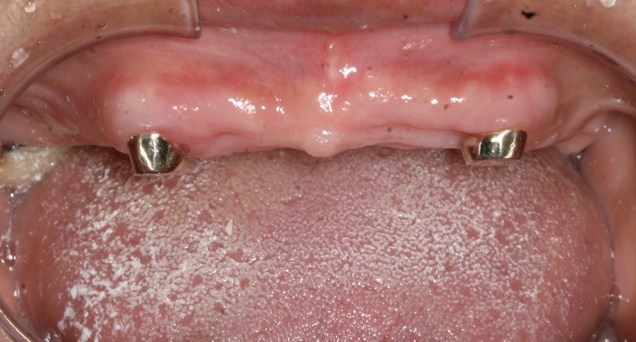

2. 磁性附着体:这种设计利用了磁铁的原理,将磁铁和铁块分别粘接到牙根及活动假牙上,通过磁力把假牙吸附在口腔内的金属部件上,就像磁铁吸铁一样,让假牙牢牢地待在该待的地方。磁性附着体一般都是在牙根上制作的。

图片12.png

图片13.png

图片14.png

.磁性附着体